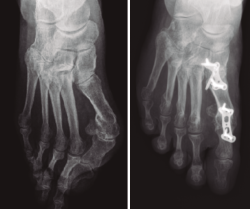

En el tratamiento quirúrgico del HV severo y considerando los conceptos expuestos previamente, unos autores promulgan la práctica de la artrodesis MTF aislada(7,8,9)(Figura 1A) y otros la práctica de la artrodesis MTF asociada a osteotomía para disminuir el AIM(10)(Figura 1B). Aparentemente, la artrodesis MTF aislada y la artrodesis MTF más una técnica que disminuya el AIM son 2 tratamientos quirúrgicos diferentes que, ante pacientes con HV severo, tienen el mismo resultado radiológico.

Figura 1. A: artrodesis metatarsofalángica; B: artrodesis metatarsaofalángica asociada a una osteotomía de cierre del ángulo intermetatarsiano.